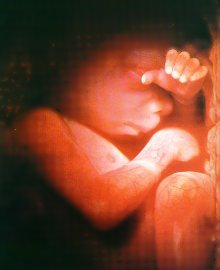

By eight weeks, the baby's arms and legs have grown longer, and the muscles have become evident.  The baby can feel and is actually capable of playing with the yoke sac.  The baby can spread its toes, move about and is very much alive.